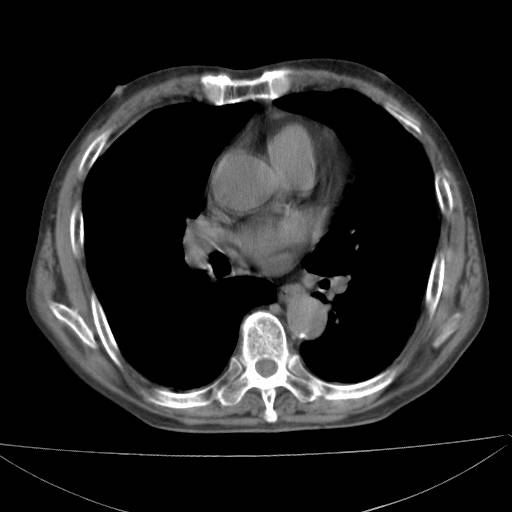

以下是引用zjzjr在2006-12-6 19:04:00的发言:[br]左肺上叶尖后段可见椭圆形高密度影,其内可见点状钙化影,周围可见卫星病灶.首先考虑结核,双侧少量胸腔积液.

以下是引用李世军在2006-12-6 19:54:00的发言:[br]左肺上叶尖后段可见椭圆形高密度影,其内可见点状钙化影,周围可见卫星病灶.首先考虑结核,双侧少量胸腔积液. [br] [br] 双肺轻度肺气肿,左肺上叶后段见多发斑片状密度增高影,周围见少许斑点状卫星病灶,双侧胸膜增厚粘连,纵隔内未见明显改变,考虑结核可能性大,请结合临床或增强扫描. [br] [br]

以下是引用13081830109在2006-12-6 19:35:00的发言:[br]左肺上叶尖后段可见椭圆形高密度影,其内可见点状钙化影,周围可见卫星病灶.首先考虑结核,双侧少量胸腔积液.

以下是引用守望可可西里在2006-12-7 0:01:00的发言:[br][quote]以下是引用zjzjr在2006-12-6 19:04:00的发言:[br]左肺上叶尖后段可见椭圆形高密度影,其内可见点状钙化影,周围可见卫星病灶.首先考虑结核,双侧少量胸腔积液.